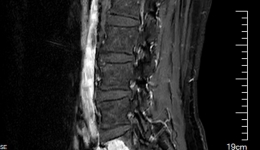

• 攻克脊柱外科“手术禁区”,我院骨科成功实施高难度腰5椎体全切术 院内新闻

攻克脊柱外科“手术禁区”,我院骨科成功实施高难度腰5椎体全切术

近日,我院骨科俞阳主任医师团队成功为一罹患脊柱肿瘤的59岁男性开展“腰5椎体全切术”。腰5椎体全切术是骨肿瘤领域顶尖、最复杂的手术之一。我院开展该手术不仅为患者解除沉疴,也体现出骨科在脊柱肿瘤高精尖的诊疗能力已达到全国领先水平。患者8...

发布时间:2025-10-16|来自:骨科